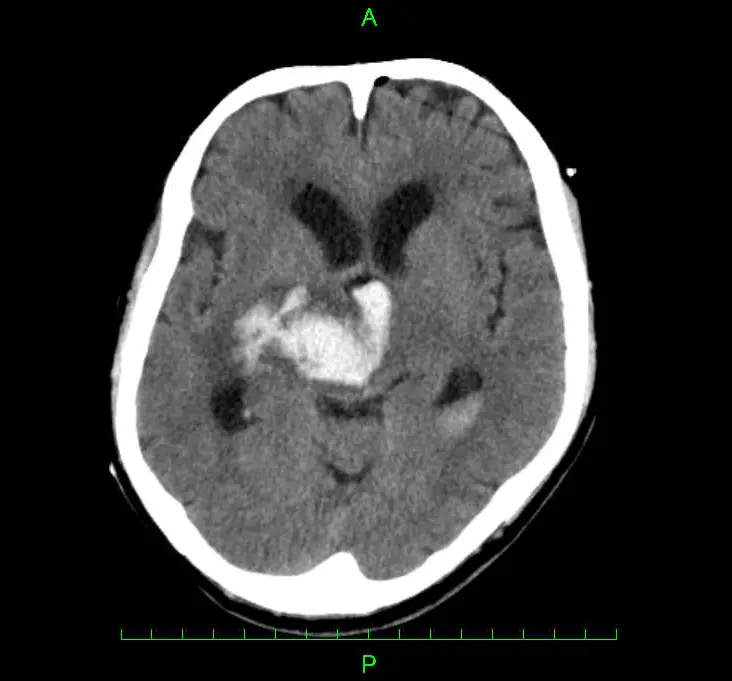

脳出血(のうしゅっけつ、脳内出血とも)とは大脳や小脳、脳幹といった脳そのものの中で出血が起こり血腫(血のかたまり)ができることを言います。原因はほとんどが高血圧によるものですが、脳動脈瘤や脳動静脈奇形、脳腫瘍などによる場合もあります。出血が起きた脳の部位により大きく5つ(視床出血・被殻出血・小脳出血・脳幹出血・皮質下出血)に分類され、それぞれ異なる症状が出現します。なお、くも膜下出血は脳の外(表面)で出血が起きる病態のため、別のものとして分類されます。

主に頭部CT検査を用います。CT検査で脳出血と診断された場合は、出血原因の特定等を目的にMRI検査や造影検査などを行う場合があります。